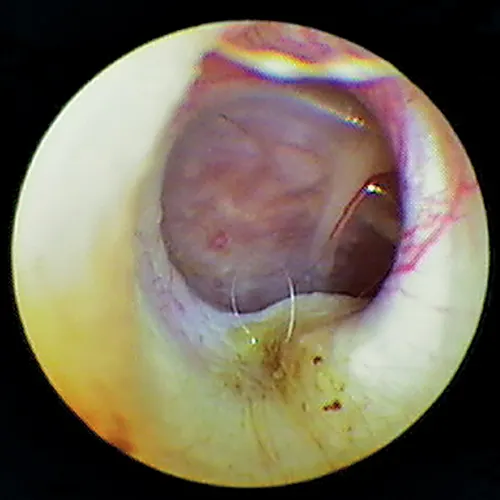

Because the normal pars tensa is translucent, the bulla cavity can be seen when enough light (using a video otoscope) transilluminates the bulla. In otitis media, fluid, if present, can be seen behind the eardrum in the form of bubbles, blood, serum, or pus. Increasing pressure from exudate accumulation can cause the pars tensa to bulge outward. Both of these conditions result in marked pain; pressure must be relieved by myringotomy. Any tissue mass in the middle ear will obscure the ability to view the middle ear (Figure 15). Occasionally, in cats, a middle ear polyp can be seen through the eardrum as a fleshy mass in the bulla.

Otoscopic image of pink mass with red striping seen behind ear drum.

FIGURE 15

Tissue mass behind the eardrum. Note the malleus bone in the pars tensa, indicating the mass is behind the eardrum.